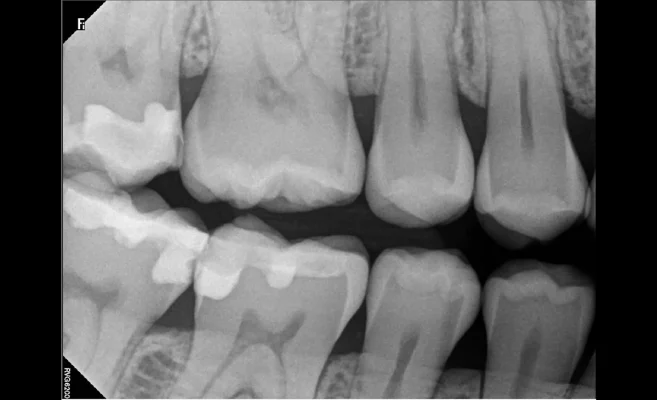

- Efektivní vyšetření s použitím rozhraní FMS

Představte si, že byste nikdy nečekali na svůj snímek. Kolik času ušetříte, jestliže Váš systém

je vždy připraven okamžitě dodat požadovaný snímek. S RVG 6200 nemusíte zakládat senzor

ani otvírat snimkovací rozhraní – systém je připraven, kdykoliv ho potřebujete. Jednoduše

vložte senzor do úst pacienta a exponujte. Snímek je ihned k dispozici.